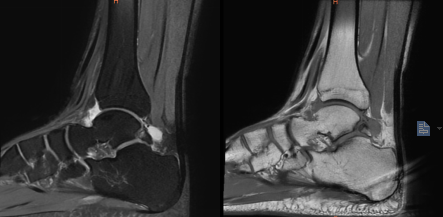

術(shù)前MRI顯示左踝副骨綜合征

一位19歲大學(xué)生,由于左踝長(zhǎng)期疼痛,輾轉(zhuǎn)多家醫(yī)院癥狀未緩解,嚴(yán)重影響其學(xué)習(xí)生活,經(jīng)人介紹來(lái)到我院骨科治療。骨科副主任(主持工作)彭李華博士為其進(jìn)行了全面專(zhuān)業(yè)的檢查,發(fā)現(xiàn)為三角籽骨綜合癥。完善術(shù)前檢查及準(zhǔn)備后,彭李華博士為患者行“踝關(guān)節(jié)全內(nèi)鏡下清理、松解術(shù)”。患者對(duì)手術(shù)效果滿意,已順利出院。